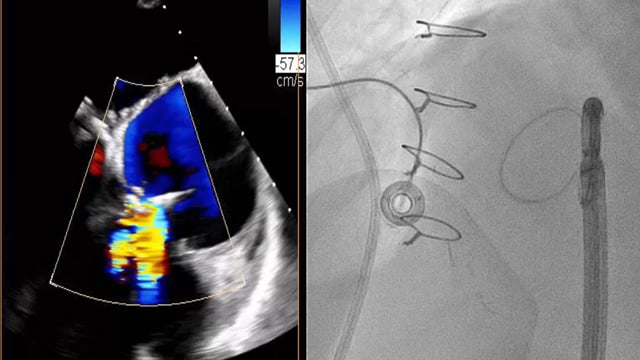

Mitral interventions in shock

17 Nov 2025 – From PCR London Valves 2025

This session highlights the intricacies of mitral valve interventions in the context of cardiogenic shock. It addresses complex cases including left-to-right shunts post septal puncture, severe ischemic mitral insufficiency with small valve anatomy, emergency mitral TEER for papillary muscle rupture, and bridging strategies to surgery.